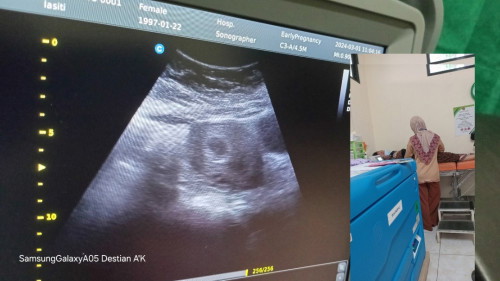

Apa wjr dok hamil 4 minggu seperti itu

Wajar kah dok hamil 4minggu baru seperti itu

Wajar ya, 4week biasanya baru penebalan dinding rahim. Kalau tespeknya positif garis 2tebal, tunggu 3mingguan lagi usg ulang (jika tidak ada keluhan). #pengalaman anak pertamaku